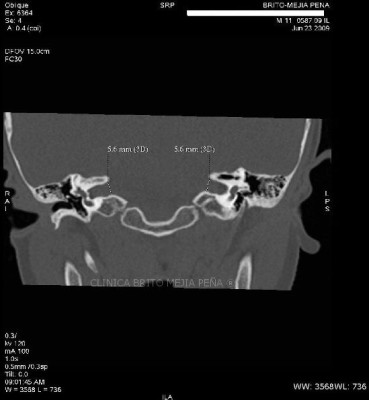

Cabeza y Cuello 2

Envíado por BMP Imágenes Diagnósticas

BMP Imágenes Diagnósticas